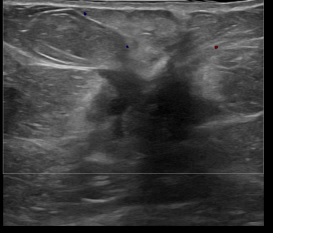

아산유외과개원후 856번째 유방암진단

상기환자는 외부건진이상소견 조직검사위해 내원하신 60대 초반

여성분으로 의심스러운 좌측혹 조직검사 시행해 유방암 진단되었습니다.